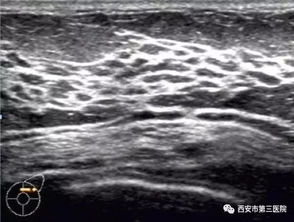

谣言二:乳腺增生会癌变

乳腺增生是一种非常常见的良性疾病,尤其在30-50岁女性中高发。很多人一听到“增生”就担心是不是癌前病变。北京协和医院的科普文章明确指出:乳腺增生≠乳腺癌,大多数情况下不需要特殊治疗,只需定期复查即可。